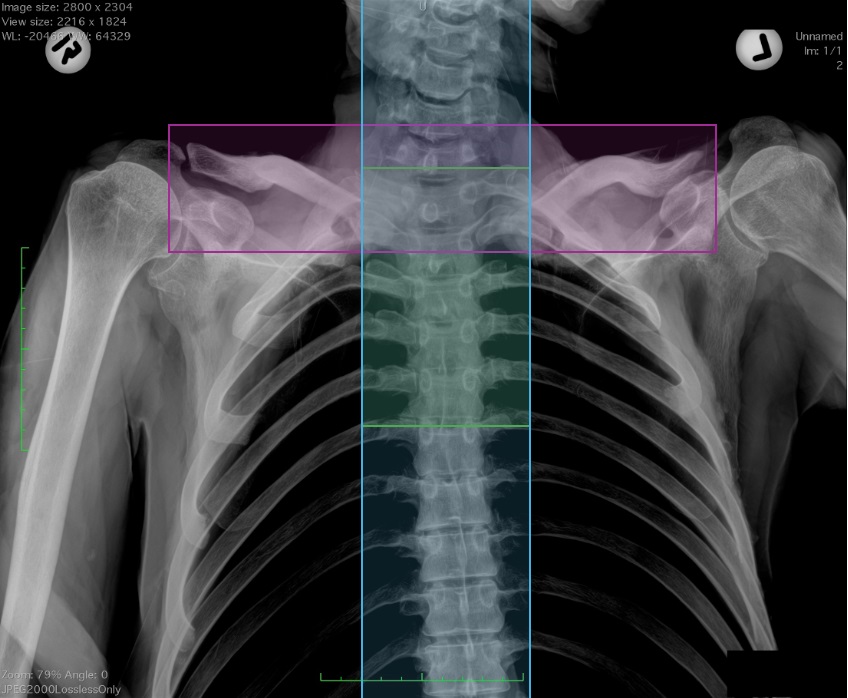

Forensic anthropologists at MSU have developed an innovative AI-driven system to significantly accelerate and enhance human identification using chest radiographs. The research is the first to assess how different regions of interest within radiographs can be used for human identification in forensic contexts.